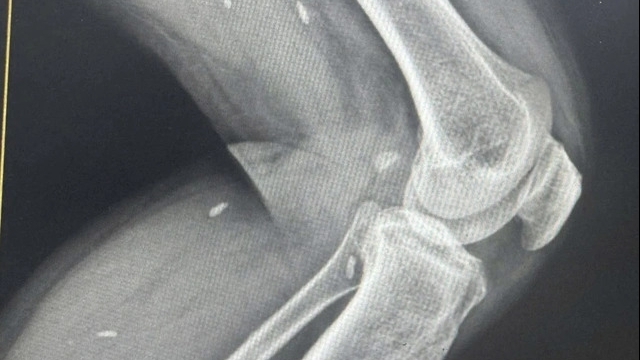

Khối u phát triển (ảnh BVCC) |

Các xét nghiệm nội soi, chụp cắt lớp cho thấy, khối u dạng sùi chiếm toàn bộ hố amidan trái và sụn nắp gây hẹp khẩu kính hạ họng.

Ngoài ra, có hạch trung thất, hạch thượng đòn hai bên với đường kính hạch lớn nhất lên đến hơn 10 cm. Kết quả chẩn đoán bệnh nhân mắc ung thư hạ họng di căn ở giai đoạn muộn.